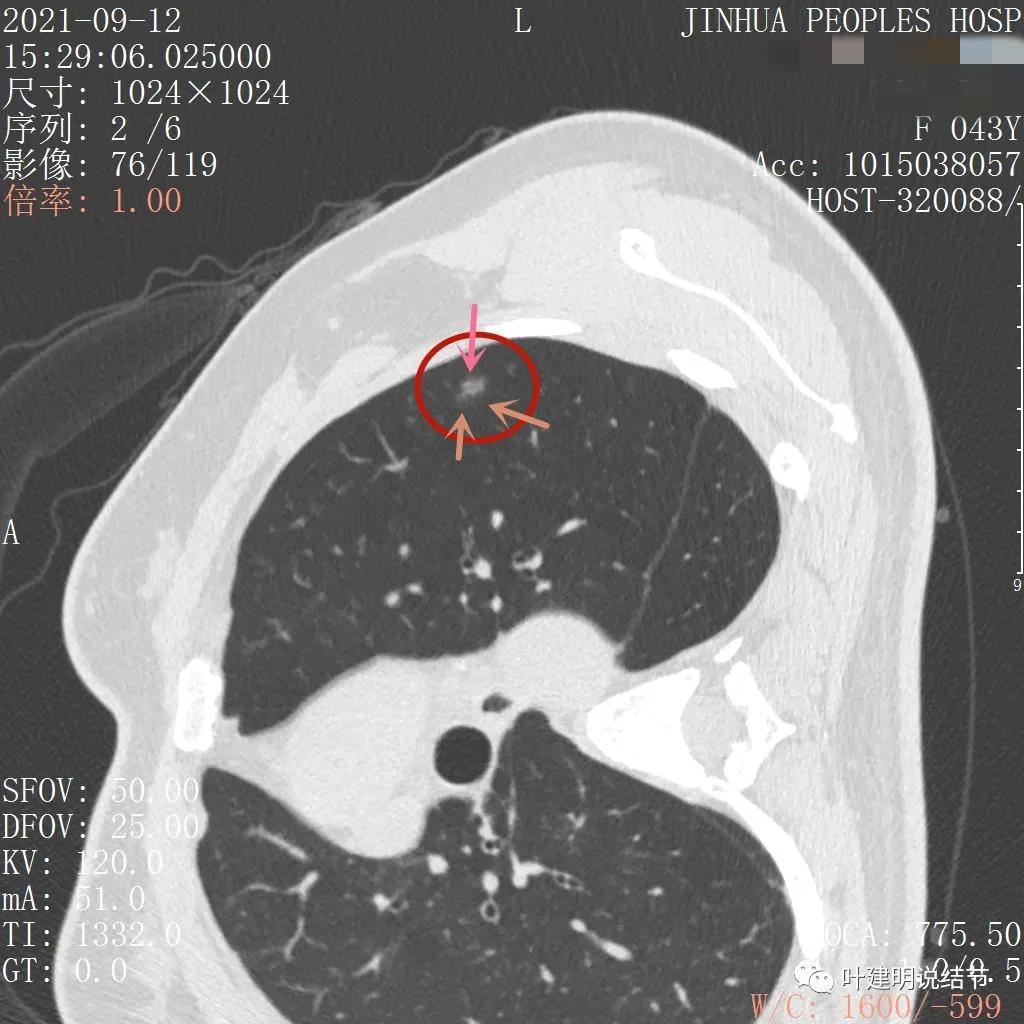

上图层面也显示病灶边缘欠清,有些模糊,虽总体轮廓还是比较清晰

从以上靶扫描图像上看,给人的印象是肿瘤范畴的结节,是混合磨玻璃结节,但磨玻璃部分的密度偏低,有的边缘显模糊,中间有点状高密度,也有微小血管进入,应该至少微浸润性腺癌可能性大。持续存在已经2月余,位置又还靠边上的,可考虑手术切除。下面再来瞧瞧后处理重建的图像:

上图非常不舒服,病灶边缘有毛刺(蓝色箭头),中间有偏实性成分(粉色箭头所指),整体看密度不均杂乱

上图示明显的血管进入(桔色箭头),而且进入病灶后散大模糊,不是穿行;病灶内有高密度区域(粉色箭头)。但事后分析,绿色箭头所指的磨玻璃部分密度仍是过低,且边缘显模糊,与浸润性腺癌可能不是太符合。

以上三图均示典型的混合磨玻璃,实性成分杂乱,整体密度杂乱,并有血管征,是较为典型的浸润性腺癌影像表现。

看了后处理重建的图像,我们认为基本上应该就是浸润性腺癌了,从平扫到靶扫到靶扫描后处理,一步一步往更恶性的角度考虑。某A按我们的建议进行了单孔胸腔镜下手术,结果术中快速病理切片示:原位腺癌。我还觉得术后病理会不会升级,所以还在等石蜡切片,因为影像上,特别是后处理重建的图像太像浸润性腺癌了,结果仍是原位腺癌: